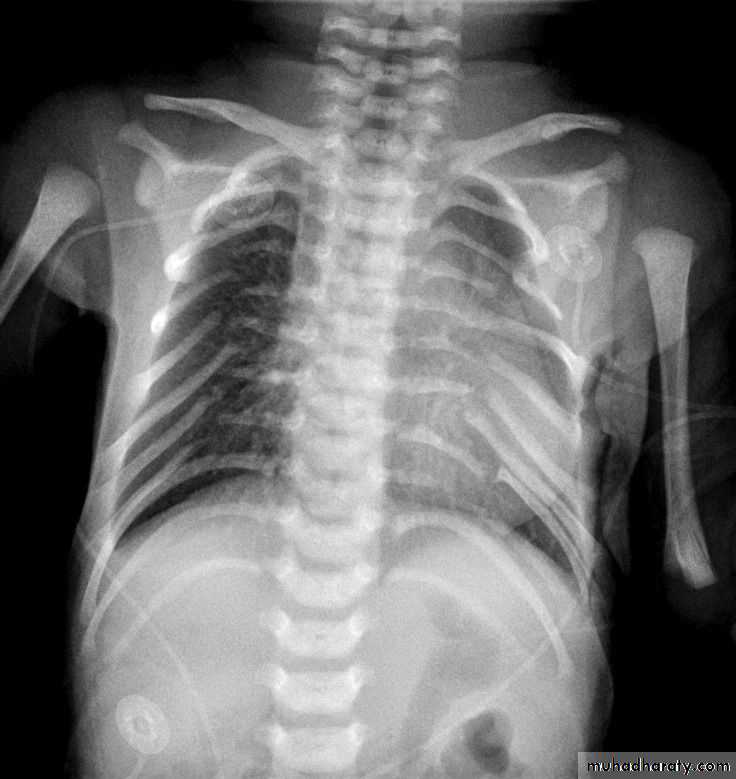

• Check up chest x-ray